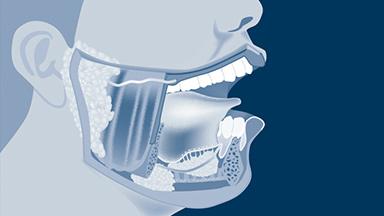

Oral physiology concerns the stomatognathic system and the functioning and interaction of the teeth, jaws, and associated tissues.

Structures of the oral cavity and associated tissues play important roles in mastication, swallowing, communication, and other functions. The components of oral physiology, although interlinked, can be divided for simplicity into various functional components such as the teeth, periodontium, and oral mucosa.